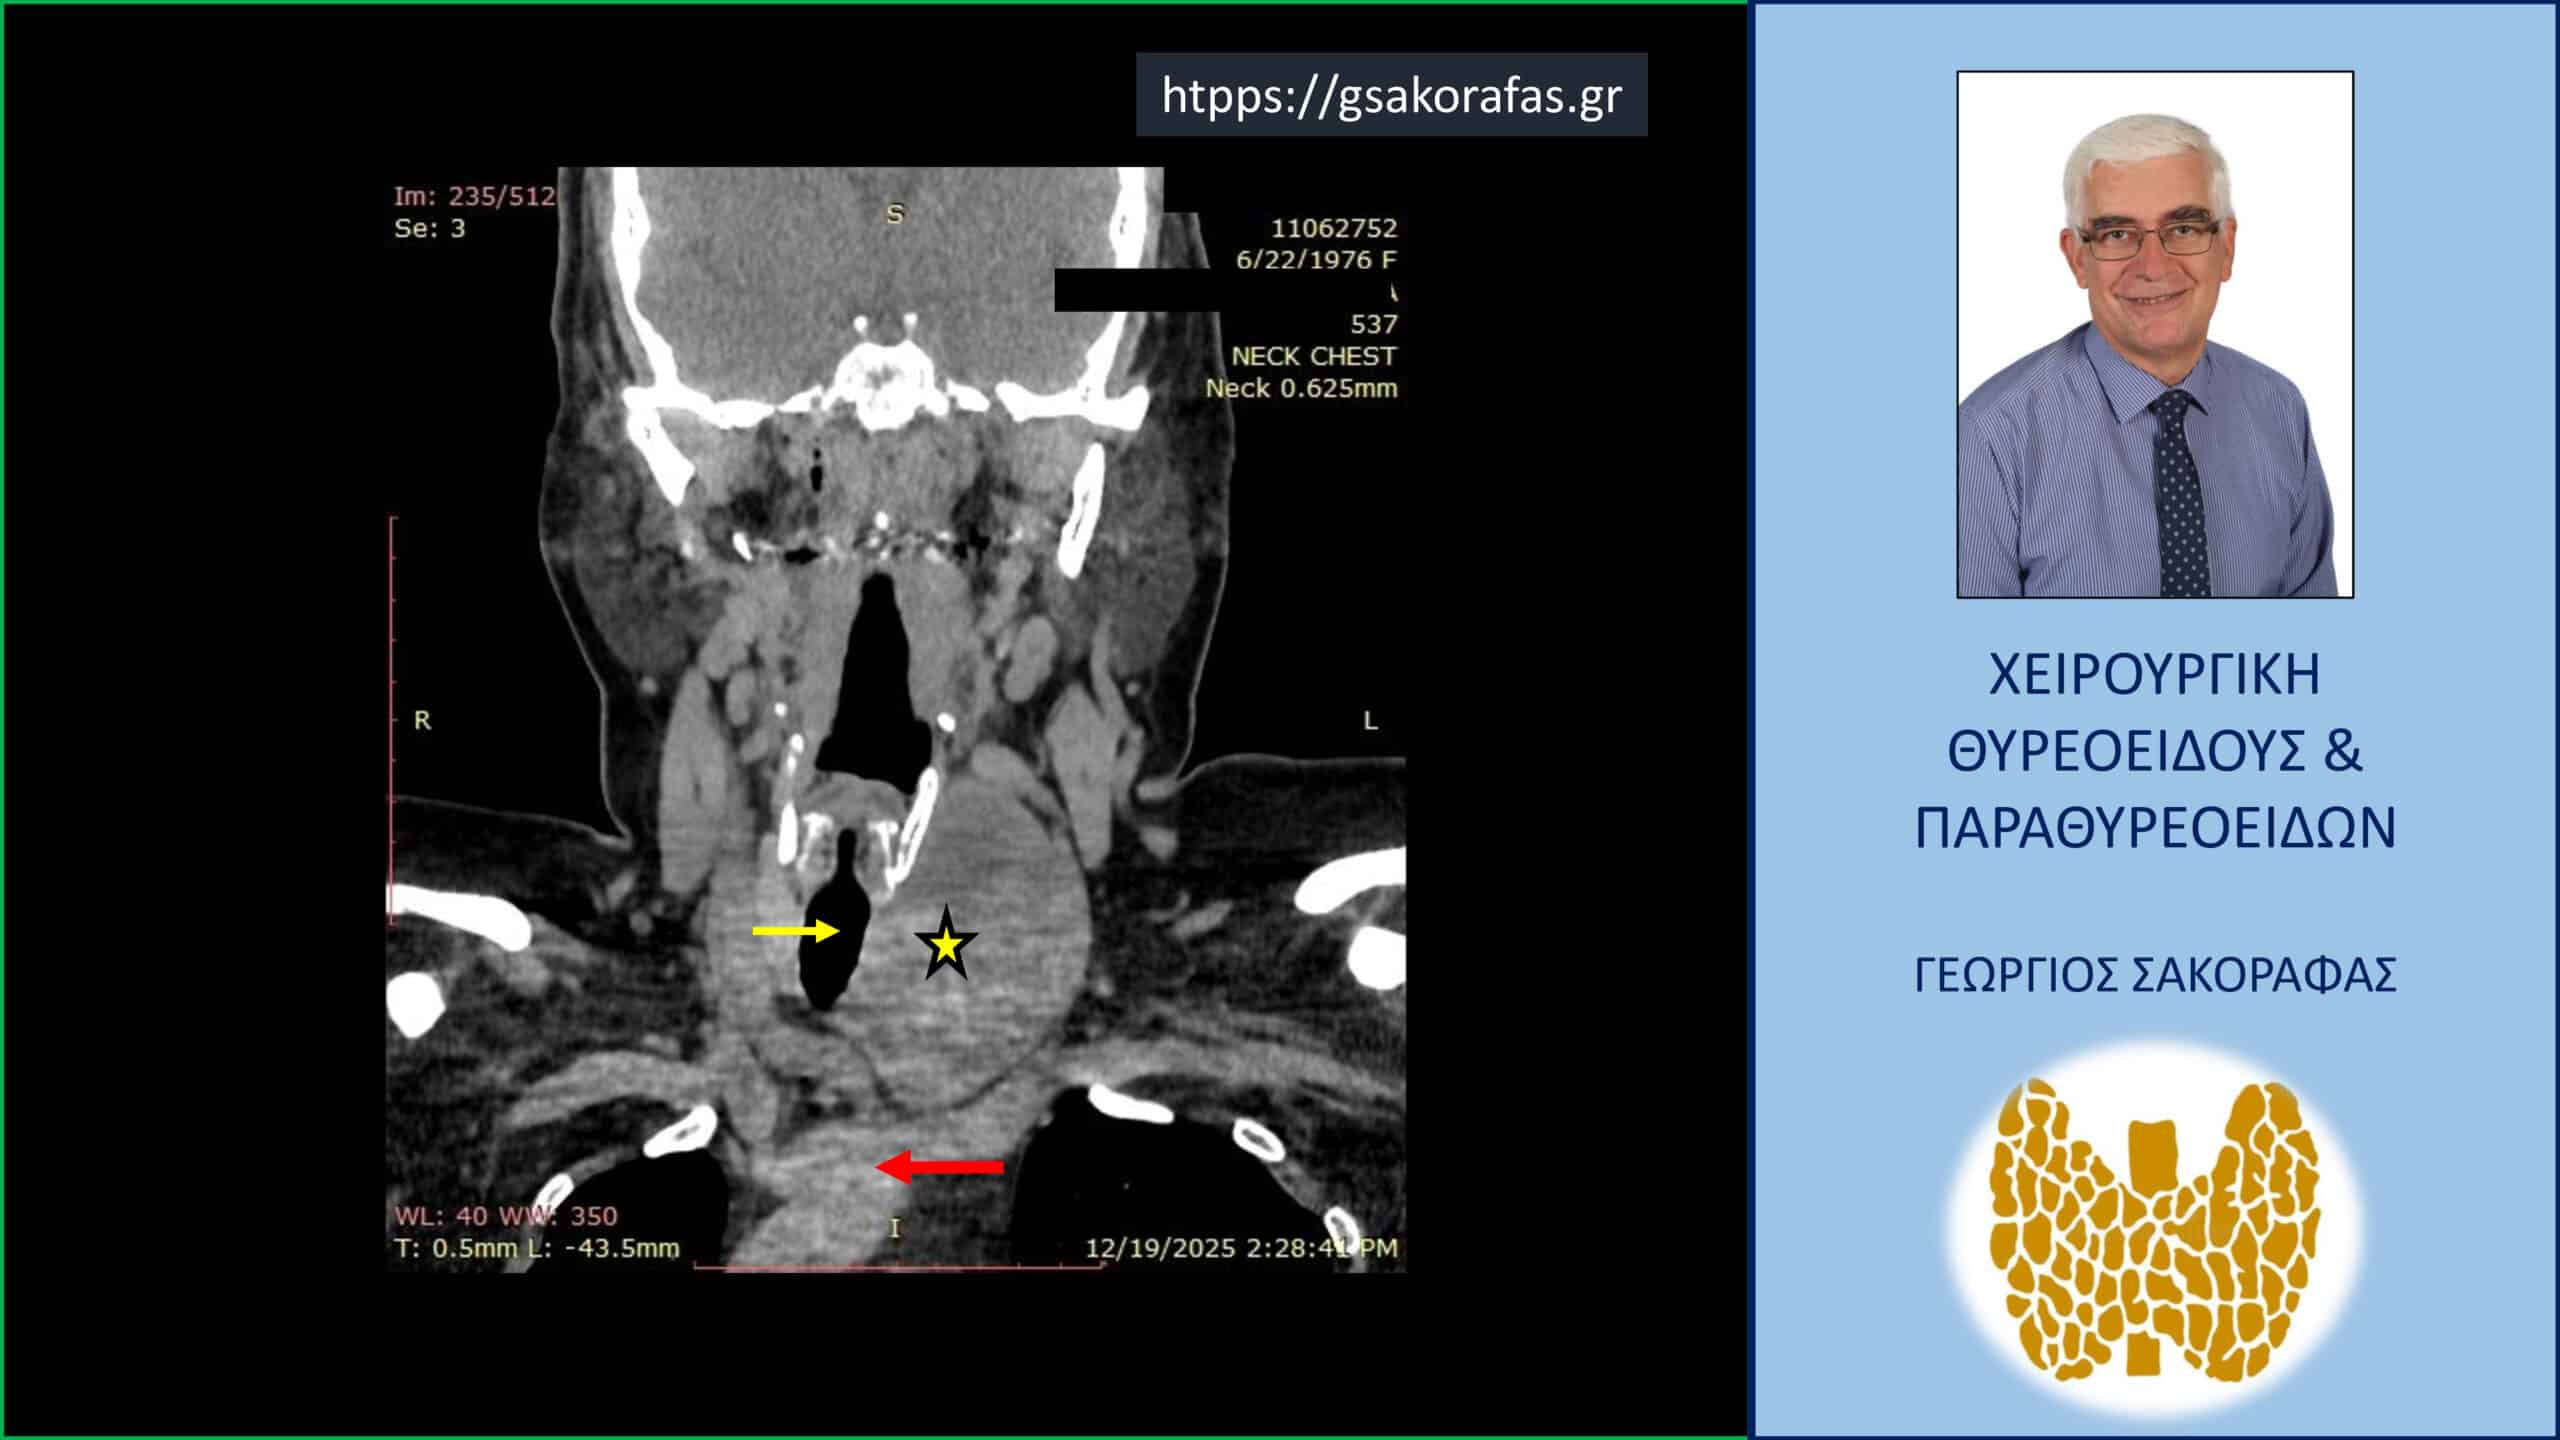

Καταδυόμενη βρογχοκήλη – αξονική τομογραφία σε κατά μέτωπο διατομή. Απεικονίζεται ο ευμεγέθης όζος (κίτρινος αστερίσκος) σε θέση κατάδυσης στο ανώτερο μεσοθωράκιο φθάνοντας στις παρυφές του αορτικού τόξου (κόκκινο βέλος) ανάμεσα από την έκφυση της ανωνύμου αρτηρίας και της αριστερής υποκλειδίου αρτηρίας, απωθώντας προς τα δεξιά την τραχεία (κίτρινο βέλος).

4.